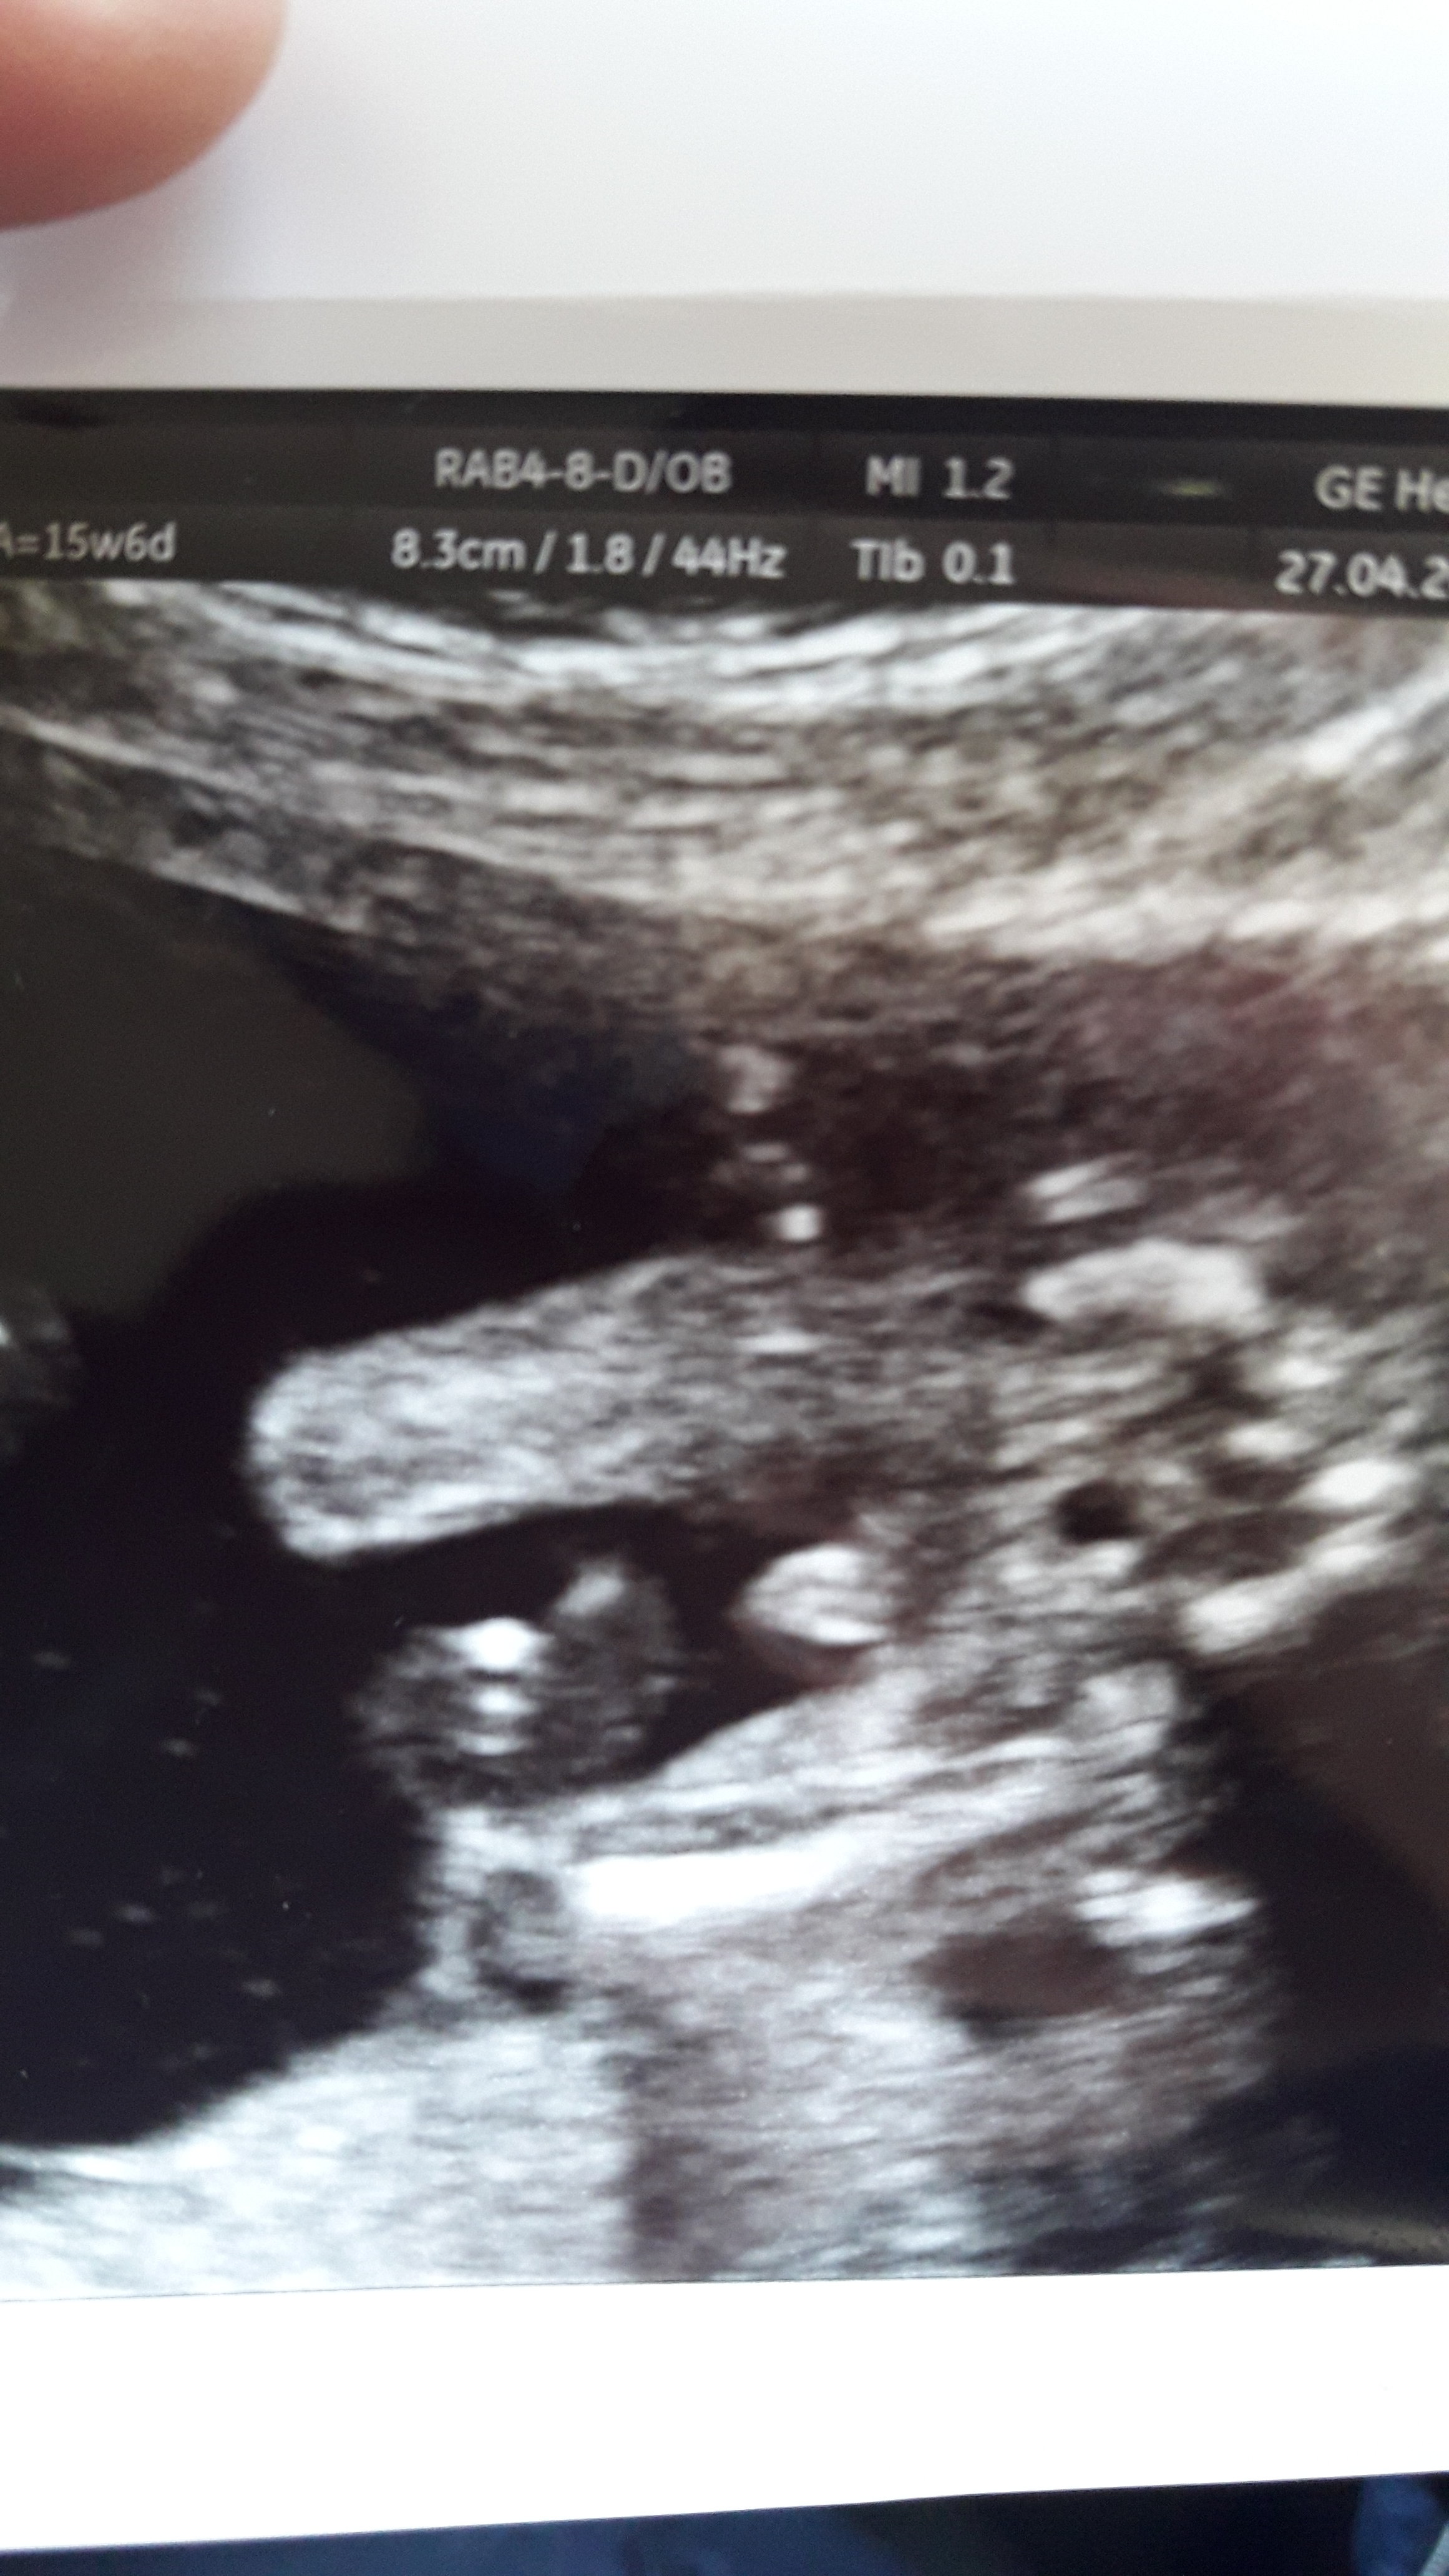

Masz tu zdjęcie mojego dla porównania

Witaj.W ostatniej ciąży mój mąż też miał takie same wątpliwości co ty. U nas lekarz w 14 tygodniu powiedział nam że to chłopiec.I też na USG widziałam takiego siusiaczka jak u Ciebie😉😉😉I tak było do końca ciąży.Urodzilam chłopca.Nic tylko się cieszyć.